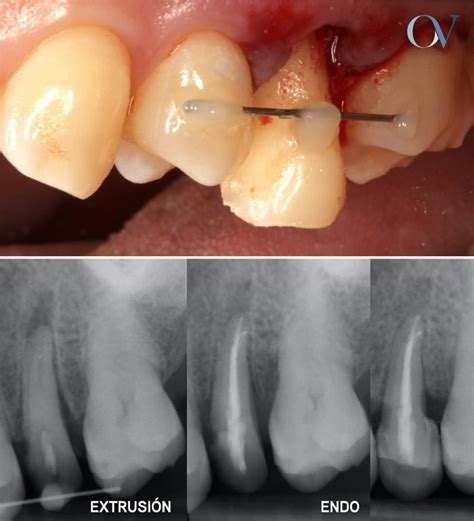

- Fracturas Dentales o Endodoncias sin Protección: Un diente fracturado o endodonciado sin la protección adecuada puede ser más susceptible a la extrusión.

- Ortodoncia: En casos de maloclusión o extrusión severa, la ortodoncia puede ser necesaria para realinear los dientes y corregir la mordida.